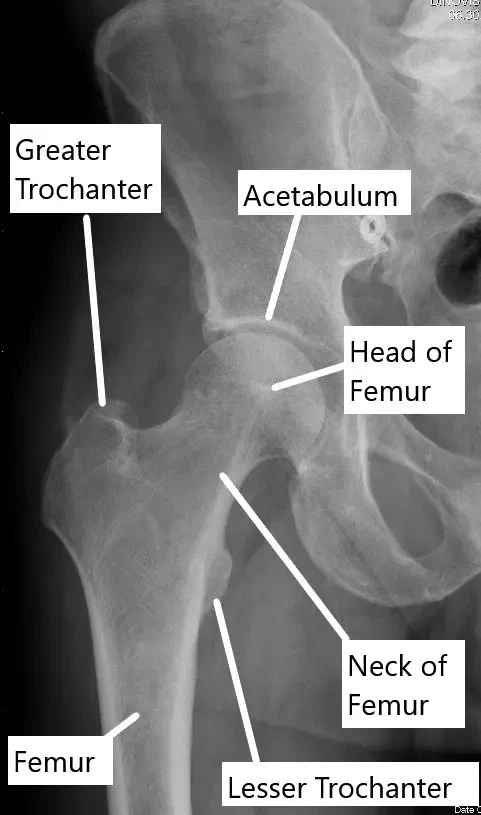

X-ray showing normal anatomy of the hip joint.

How the Body Part Normally Works? (Relevant Anatomy)

The hip joint is a ball-and-socket joint where the femoral head (ball) fits into the acetabulum (socket) of the pelvis. The joint is stabilized by a capsule of ligaments and muscles, and the surfaces are lined with cartilage that allows smooth movement. In transient osteoporosis, the femoral head loses its density and becomes more prone to pain and injury, especially during weight-bearing activities.